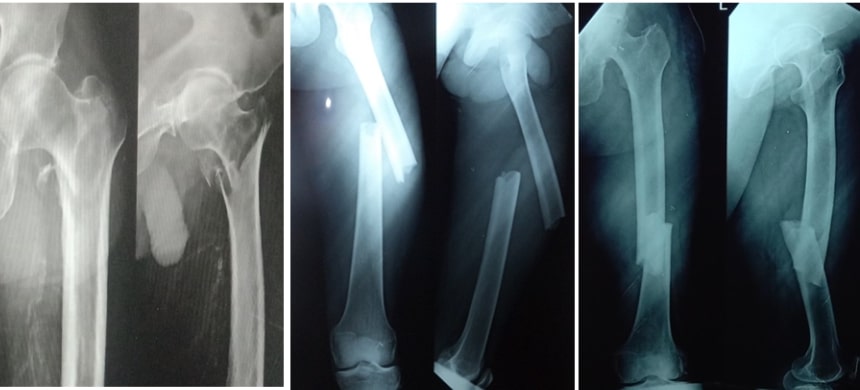

If a displaced fracture comes out of the skin or the fracture fragment is piercing the skin and coming out of the internal environment it is called an open fracture. This kind of open fracture has got a high risk of getting an infection because it is exposed to the external environment which contains dust, soil and bacteria. So, this contaminated fracture has got a lot of chances for going for non-union that means not getting united. So, this kind of open fractures need debridement for cleaning of the wound as well as cleaning of the fracture site and fixation of the fracture using modern implants or fixators. These open fractures need very good care so that in these kinds of situations we do keyhole surgeries also.

Making a small hole and fixing the fractures through the small hole by using plate, screws or nails is called minimally invasive surgery or keyhole surgery. As we are not opening the fracture site, we are not damaging any muscles, nerves or blood vessels around the fracture. We keep the internal environment of the fracture intact. So, the healing of the fracture will be quick and there is no loss of blood in this kind of Keyhole surgeries. The invention of C arm machines and the latest surgical equipment's made keyhole surgeries possible in orthopaedic field.

Most of the fractures of the leg bones are operated and fixed using this keyhole surgery. Most of the fractures of arm and forearm are fixed with plate and screws. Intra-articular fractures are the fractures involving the articular surface of bones. They need to be reconstructed properly. They should be fixed with proper implants. This fixation is very important to get back the moments of any joint.